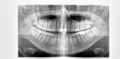

Определяющим при постановке диагноза является рентгенологическое исследование. На снимке обнаруживается зона разрежения костной ткани, которая очень четко очерчена и имеет обычно округлую форму.

Если у пациента была обнаружена гранулема, лечение следует начать как можно раньше, в этом случае удастся спасти зуб. Решение о методике лечения врач принимает в каждом конкретном случае, после тщательного исследования больного зуба и обязательного рентгенологического исследования. Помните: без рентгена невозможно диагностировать гранулему.